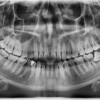

Penggunaan radiografi panoramik dapat dianggap sebagai pilihan yang sesuai untuk penegakan kasus kista dentigerous. Namun, CT scan dapat dipertimbangkan pada kasus lesi yang lebih luas, untuk mendapatkan gambaran yang lebih rinci dan detail, dengan lapang pandang yang lebih luas. Selain itu, kadang MRI dapat dipertimbangkan untuk mempertajam definisi dari lesi.

Pada pemeriksaan radiografis, kista dentigerous akan muncul sebagai area radiolusen unilokular, terkait hanya dengan mahkota gigi yang belum erupsi, dan berada pada area cemento-enamel junction (CEJ). Umumnya, batas radiolusen terdefinisi dengan jelas dan terkalsifikasi.

Hubungan kista dengan mahkota gigi menghasilkan variasi radiografis, termasuk variasi sentral, lateral, dan circumferential. Beberapa kista dentigerous dapat menyebabkan pergeseran gigi yang terlibat, bahkan mungkin ke batas bawah korpus atau ke dalam ramus mandibula.[17,18]